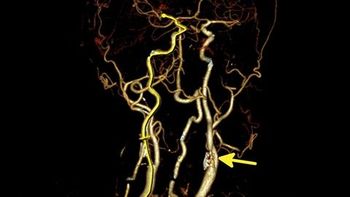

Using radiomics to assess impact of unconventional risk factors, including cocaine use and HIV infection, potentially introduces a “brave new world” of precision phenotyping in CAD.